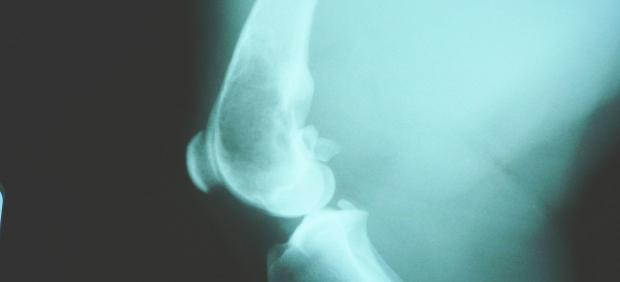

El osteosarcoma es el cáncer de huesos más común en niños. También llamado sarcoma osteogénico, es un tumor derivado de las células que generan el hueso. Pese a ser un tumor poco frecuente, es el sexto tipo de cáncer infantil en frecuencia, representa el 3% de los casos de cáncer pediátrico y se diagnostican cuatro nuevos casos al año por cada millón de niños.

Este tipo de cáncer tiende a ocurrir en los huesos más grandes del cuerpo como la espinilla, el muslo o el brazo, donde el crecimiento óseo es más rápido. Pese a ello, puede comenzar a su crecimiento en cualquier otro hueso, extendiéndose después al resto. A veces también se propaga (o hace metástasis) a otras partes del cuerpo, generalmente, los pulmones.